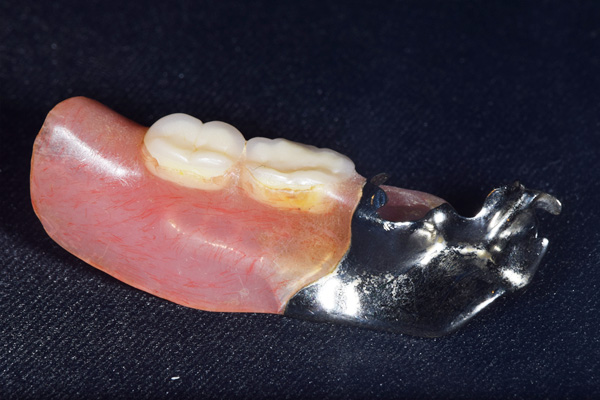

ケース3(インプラントを用いた部分入れ歯)

右上と左下の歯がない方です。 上の入れ歯の安定が悪く、作り直したいとのことでいらっしゃいました。 今お使いの上の入れ歯を見てみると、口蓋部分が抜けており、安定性に欠ける構造になっていました。この入れ歯はノンメタルクラスプデンチャーといって、金属のバネを使用しない 入れ歯になります。これは見た目は良いのですが、歯への負担が大きいことと、入れ歯自体がやわらかいため、噛むには不便なことがあります。

入れ歯は極力薄くするために金属を使用しました。しっかり噛める様にするため、ノンメタルクラスプデンチャーにはしませんでした。

上の入れ歯(表)

上の入れ歯(裏)

下の入れ歯

治療内容 レントゲンをみて最低限の長さのインプラントを右上の奥歯の位置に埋入しました。インプラントと骨の結合(オッセオインテグレーション)と歯肉の治癒を待ち、アバットメントをいれて型取りをして、入れ歯を作成しました。極力薄くするために、金属をもちいた入れ歯にしました。